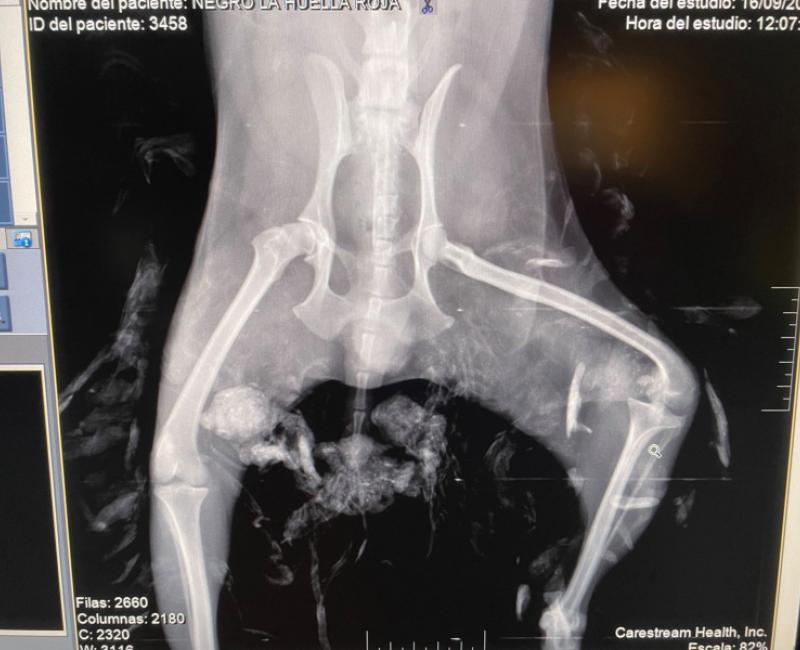

Lun, 09/30/2024 - 12:00 Nuestro querido Bob Marley nos dejo en Septiembre. A veces se nos olvida que su vida es más corta que la nuestra y que lamentablemente, en algunos casos, su final será a nuestro lado, y no en un hogar definitivo. Descansa en paz pequeño. Bob Marley